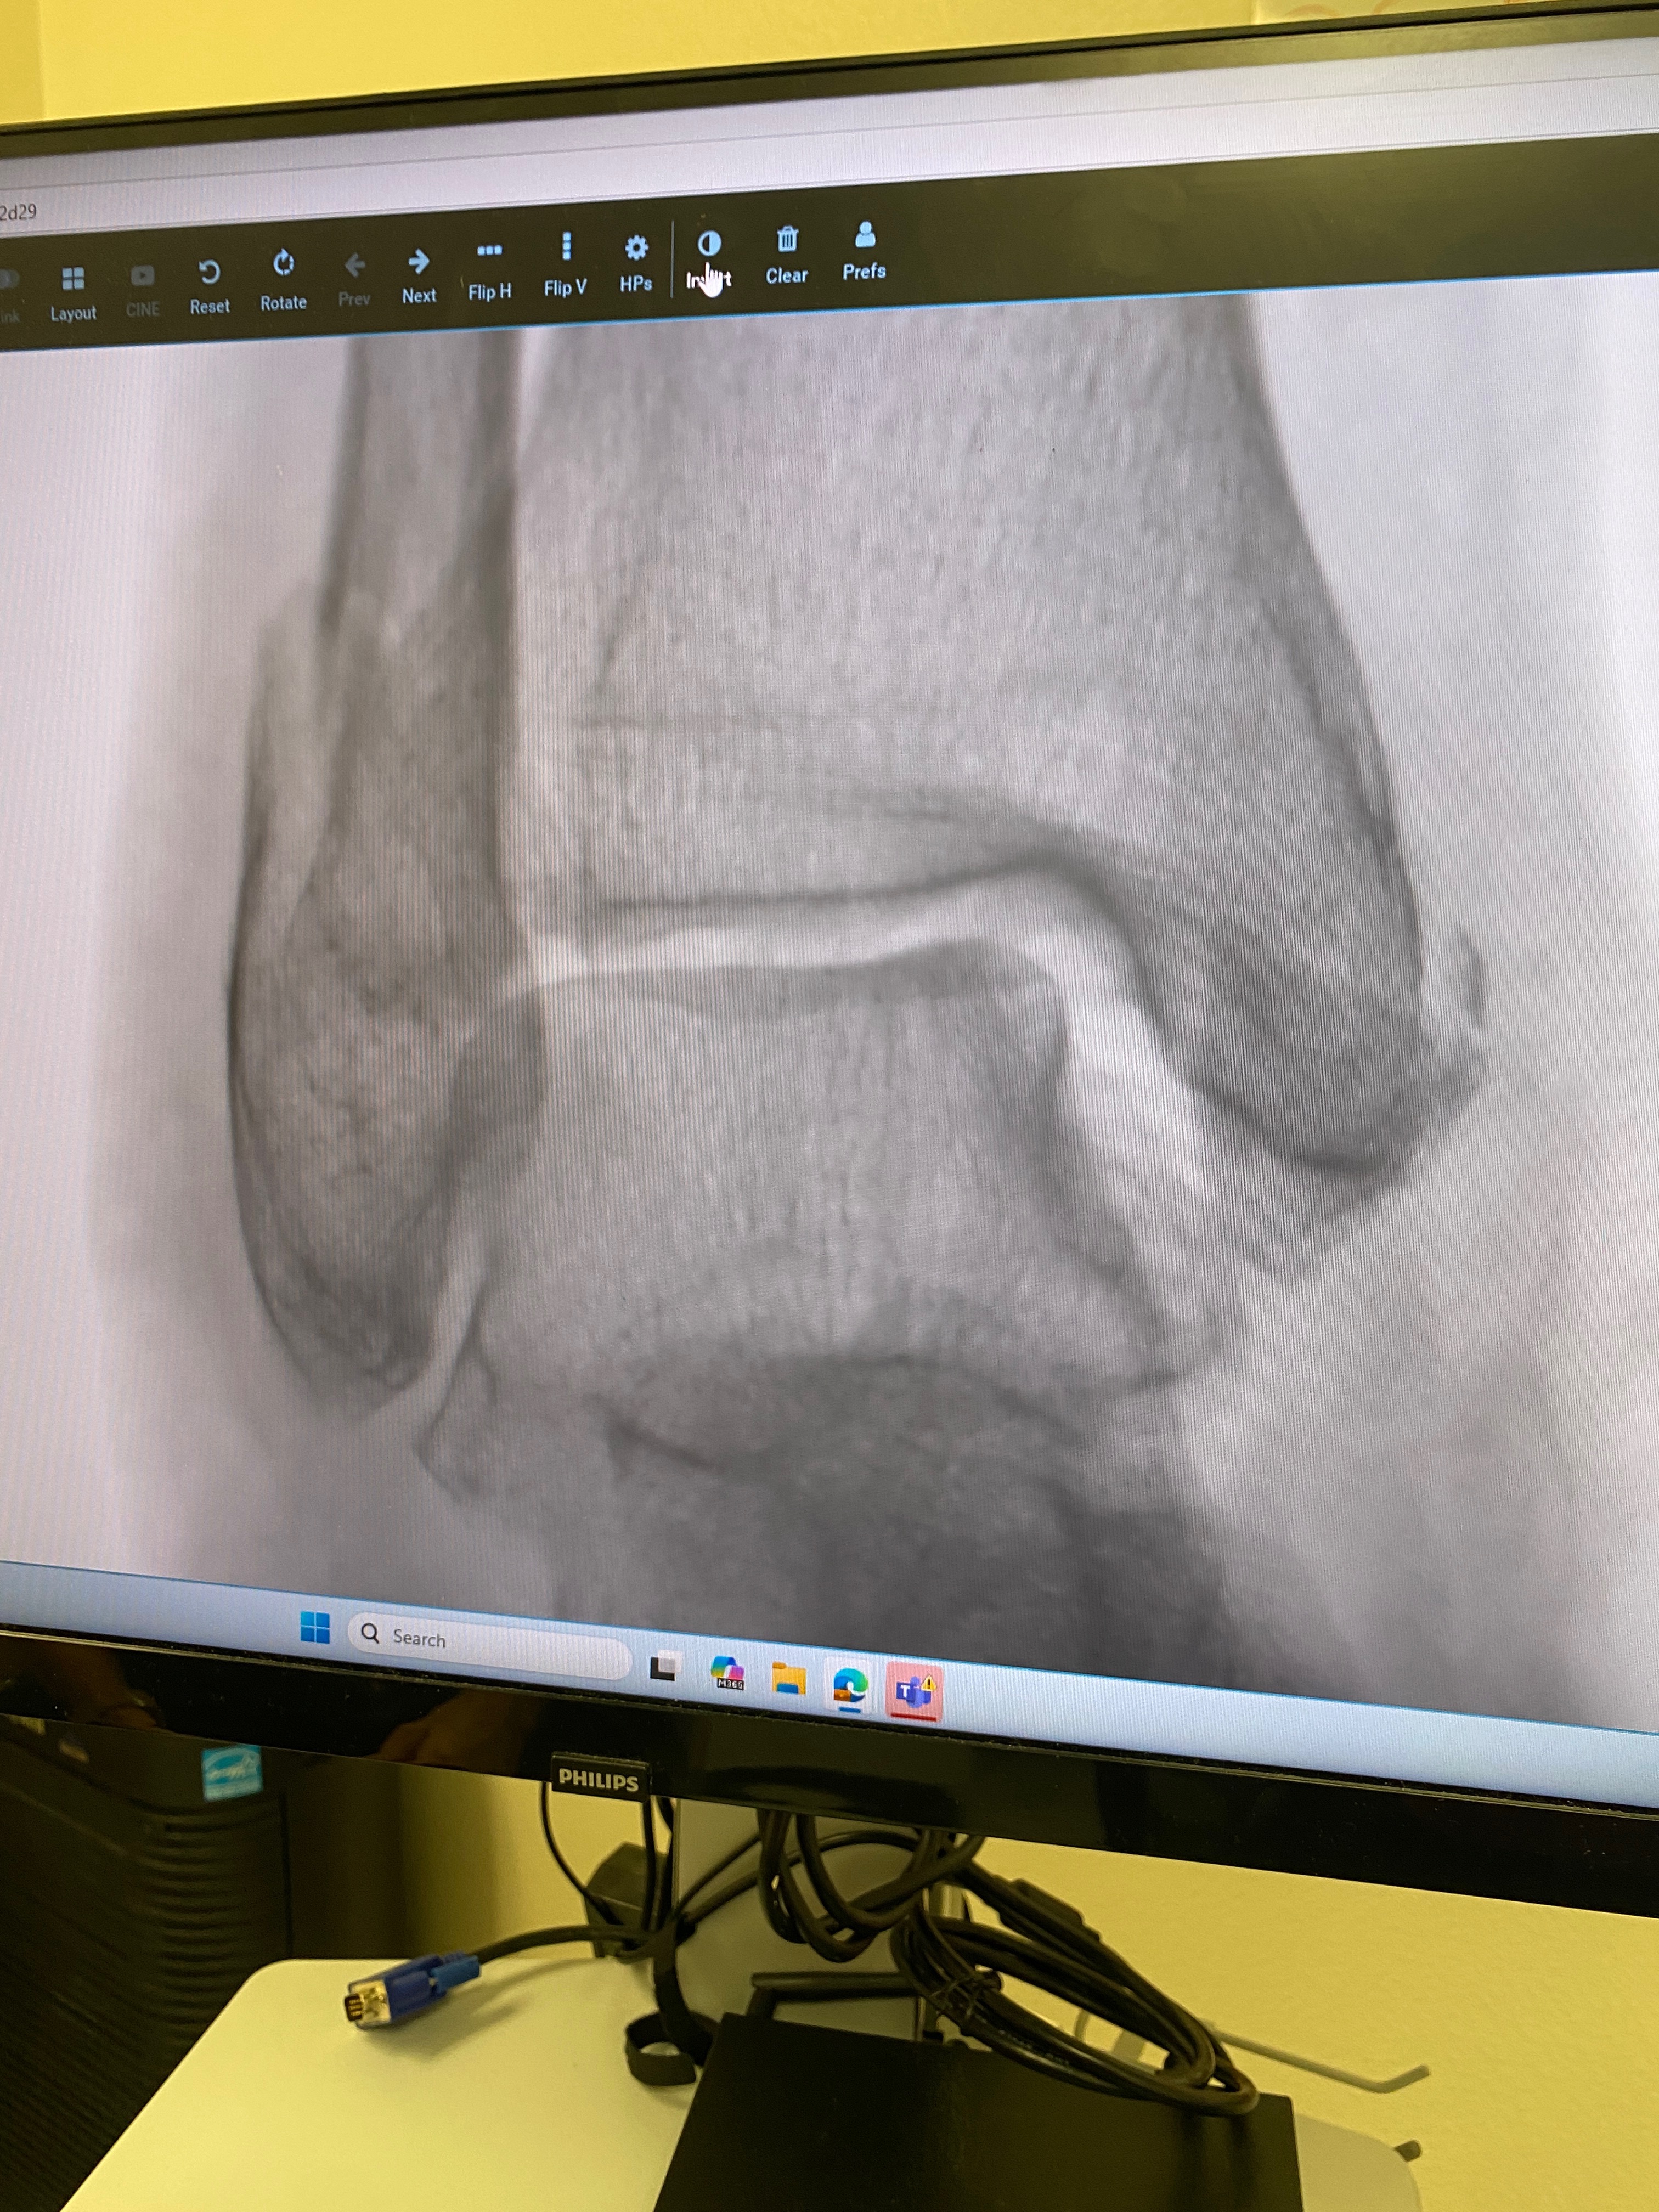

Recientemente, nuestra vida dio un giro inesperado. Mi mamá sufrió una dolorosa fractura grave en el tobillo que requiere una cirugía urgente y compleja para corregir el daño y evitar complicaciones a largo plazo. Sin esta operación, su capacidad para caminar y llevar una vida normal estará gravemente comprometida.

• Tornillos y placas necesarios para la reconstrucción del tobillo.